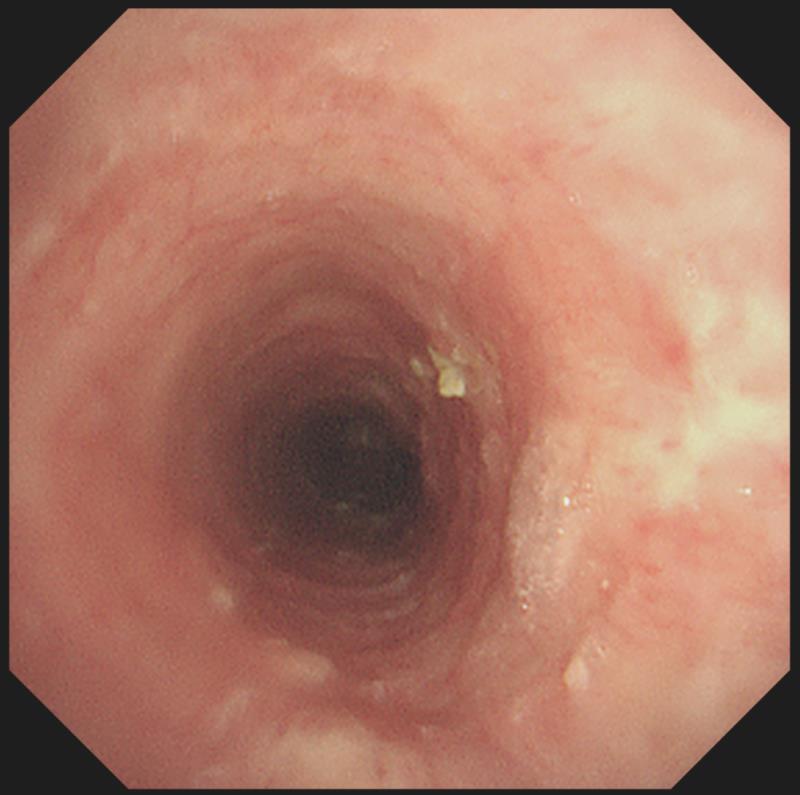

在武汉市肺科医院内镜中心,医生通过呼吸内镜进入小梁的气管、支气管进行检查发现,从咽喉到气管、左右支气管,密密麻麻长满了干酪样的结核病灶。所幸,经过积极的药物和气管镜介入治疗,小梁的病情迅速得到了控制。